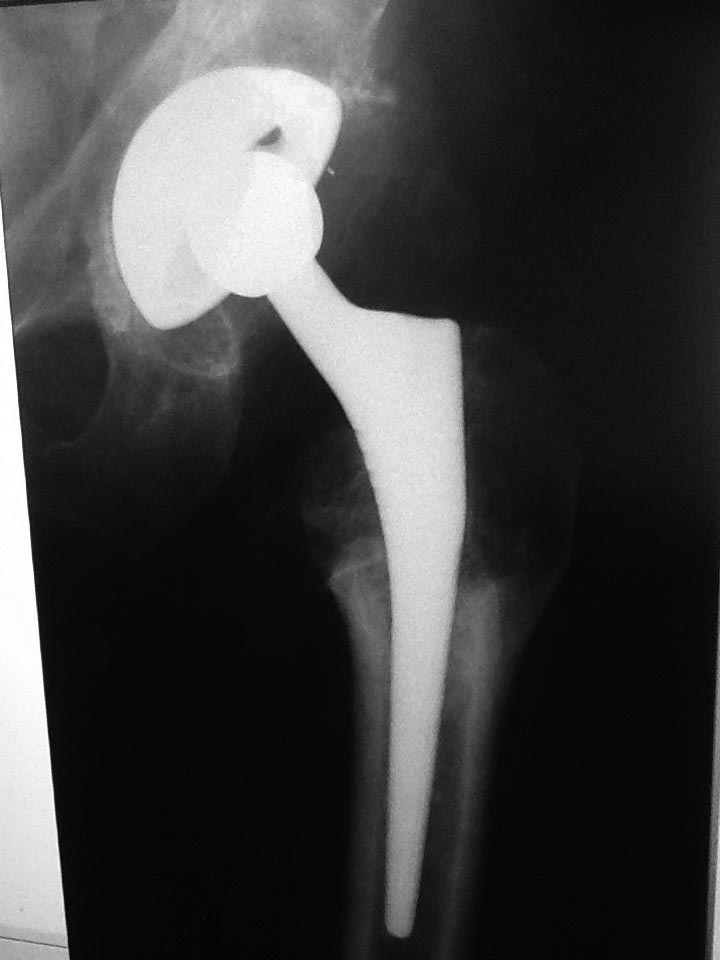

Прямая проекция